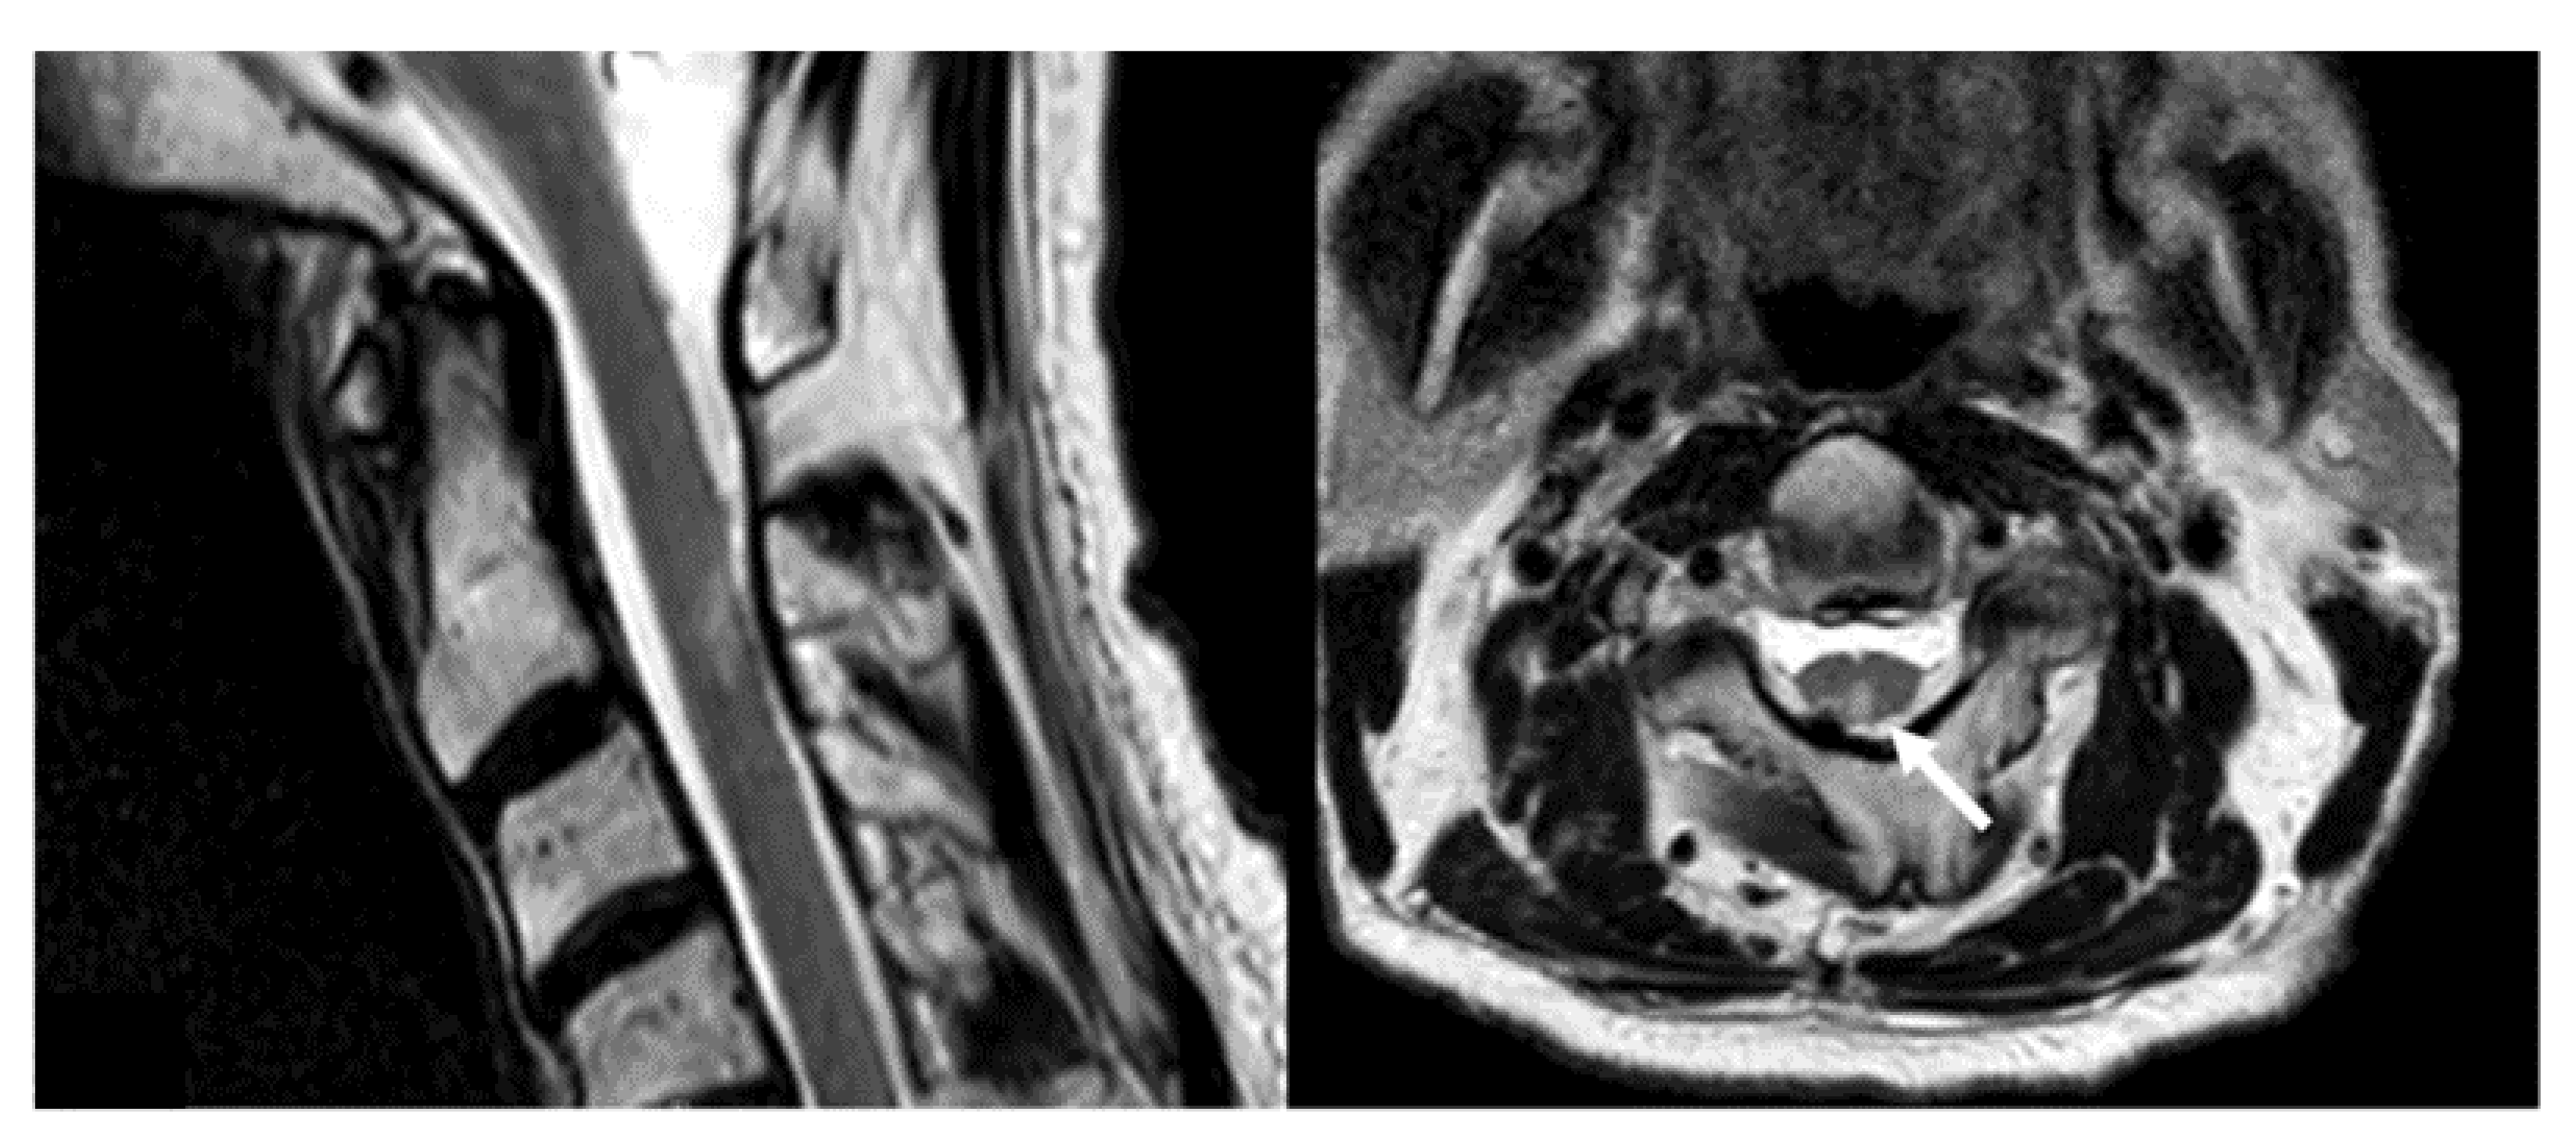

- Grauer, O.; Jaber, M.; Hess, K.; Weckesser, M.; Schwindt, W.; Maring, S.; Wölfer, J.; Stummer, W. Combined intracavitary thermotherapy with iron oxide nanoparticles and radiotherapy as local treatment modality in recurrent glioblastoma patients. J. Neurooncol. 2019, 141, 83–94. [Google Scholar] [CrossRef] [Green Version]